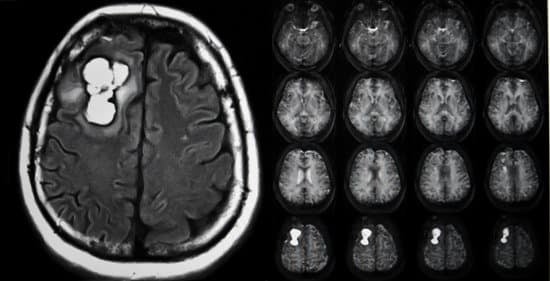

2. 영상 진단

자기공명영상(MRI): 글리오마의 진단에서 가장 중요하고 흔히 사용되는 영상 진단 방법입니다. MRI는 종양의 위치, 크기, 그리고 주변 조직과의 관계를 자세히 보여줄 수 있습니다.

컴퓨터단층촬영(CT) 스캔: MRI 사용이 어려운 경우나 긴급 상황에서 CT 스캔을 사용할 수 있습니다. CT는 빠르게 종양의 존재를 확인할 수 있으나, MRI보다는 상세도가 떨어집니다.